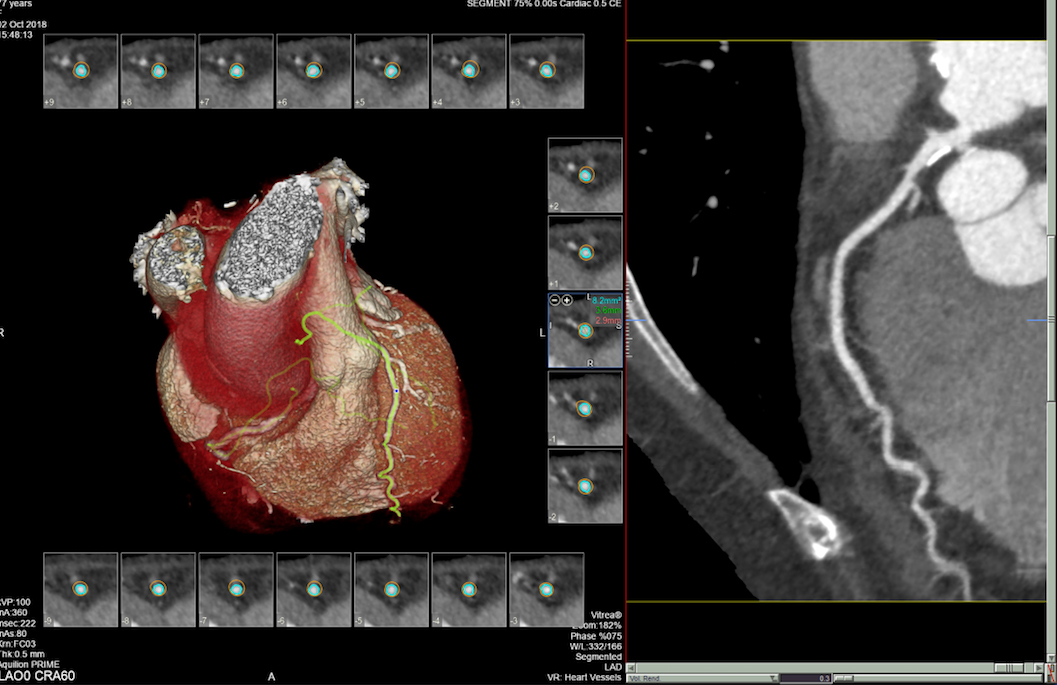

• MSCT koronarografija (prikaz krvnih žila srca CT-om, bez neugodnosti i komplikacija koje nosi klasična koronarografija), u saradnji s Poliklinkom dr.Al-Tawil